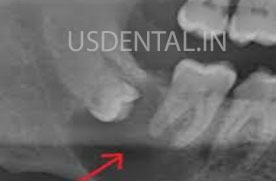

5) Impacted tooth: impacted teeth are those which do not emerge into the mouth but submerged inside the bone and gums. It’s not visible in the mouth. Impacted teeth cause pain and swelling in certain cases. Also, there are chances of formation of cyst or tumor in rare cases around impacted teeth. Cyst and tumor can damage roots and bone if not get treated at earlier stage.

Wisdom teeth which are properly positioned inside the mouth and not causing any problem no need to remove that. If you are having any of the above symptoms, you can visit the dentist for a checkup and x-ray.